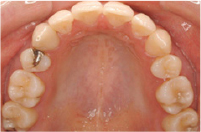

| 初診時年齢 | 23歳 |

|---|---|

| 主訴 | 口元が出ているのが気になる |

| 診断名 | 叢生を伴う上顎前突 |

| 治療に用いた装置 | リンガルブラケット矯正装置 |

| 抜歯部位 | 上下左右4番抜歯 |

| 治療期間 | 2年3ヶ月 |

| 費用の目安 | 約800,000円 |

| リスク副作用 |

治療前

治療後